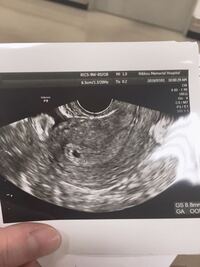

妊娠4週5日目(高温期19日目、生理予定日5日後)のエコー写真 この日、先生からいただいたエコー写真を掲載しておきます。 妊娠4週5日目のエコー写真がこちら↓↓ 真ん中の下の方に、黒い豆粒みたいなヤツがあるのわかります? これが胎嚢らしきもの?妊娠週数と胎嚢、胎芽の大きさ i)妊娠4週5日~5週0日 胎嚢(赤ちゃんの入る袋)の大きさが6mm ii)妊娠5週3日~5週4日 胎嚢の大きさが11mmで、胎嚢の中に小さなリング状のもの(卵黄嚢:赤ちゃんの栄養源)が確認されます。 こんにちは。いつも拝見しています。 今回3回目のicsiでようやく陽性判定をもらい、 昨日5週1日でエコーでしたが胎嚢が6mmでした。 凍結胚盤胞移植なので日数に狂いはありません。 医学書やネット公開の胎嚢の大きさをみてると 5週1日は10mmくらいが平均のように思います。

妊娠 心拍は確認できたが胎嚢が小さい 先週、5週0日で5ミリの胎嚢が無事に確認され、 本日、6週0日で胎嚢の中に小さな点のような 赤ちゃんが見え、かすかに心拍も確認できました。 ただ、胎嚢が4週 質問No 4週0日で何も見えず、5週0日で胎嚢確認。その後7週0日 で心拍を確認する予定でしたが、5週の時に自転車で転 倒し心配だったので受診したら39mmの胎芽がウニョウ ニョ動いていました。5週6日でした。 初診が早すぎたので、3回目で8w5dでした。流産でしょうか 体外受精で7週0日 胎芽4mm 卵黄嚢はびっくりするほど Okwave 5週 胎嚢 大きさ 4ミリ 5週 胎嚢 大きさ 4ミリ5w2dの胎嚢の大きさ 不妊治療の体外受精周期中に自然妊娠した26歳です 不妊 教えて Goo

11年7月に初めて妊娠しましたが、ケイリュウ流産でした。 そのときの胎嚢は5週4日で81ミリでした。 11年9月に再び妊娠し、現在は8ヶ月になる女の子のママです! そのときは最初の初診5週0日で3ミリしかなく、「小さい」と言われました。ネットで調べて 5週0日でこの大きさは小さいですか? 流産してしまう確率は高いのでしょうか。 5週0日だと平均6 5週目の胎嚢の直径は5~15mmくらいです。 5週後半くらいから約2~3mmの胎芽 が見え始めます。